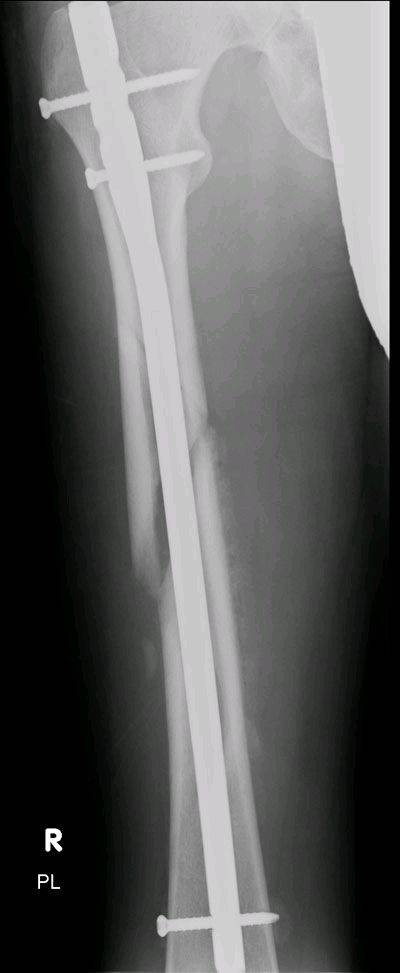

This one took 7 months to heal until I could go kiting again.

I broke my femur 500 meters off the Port Douglas beach 2 years ago.

During a jump I came out of one strap and couldn't get out of the other quickly enough. The board acted as an extension of my leg, which snapped into 2 pieces.

Before:

After: